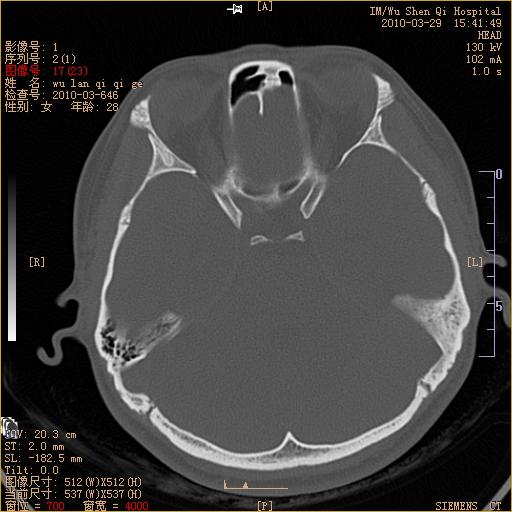

标题: CT25398:女,左耳流脓两年余,带有异物 [打印本页]

标题: CT25398:女,左耳流脓两年余,带有异物

左侧中耳乳突炎,不排除胆脂瘤形成。

左侧中耳乳突炎,胆脂瘤形成。

左侧中耳乳突炎,不排除胆脂瘤形成

1)左侧慢性中耳乳突炎并肉芽肿(或胆脂瘤)形成。2)考虑左侧颞骨慢性炎症伴骨质增生硬化,不排除骨纤。